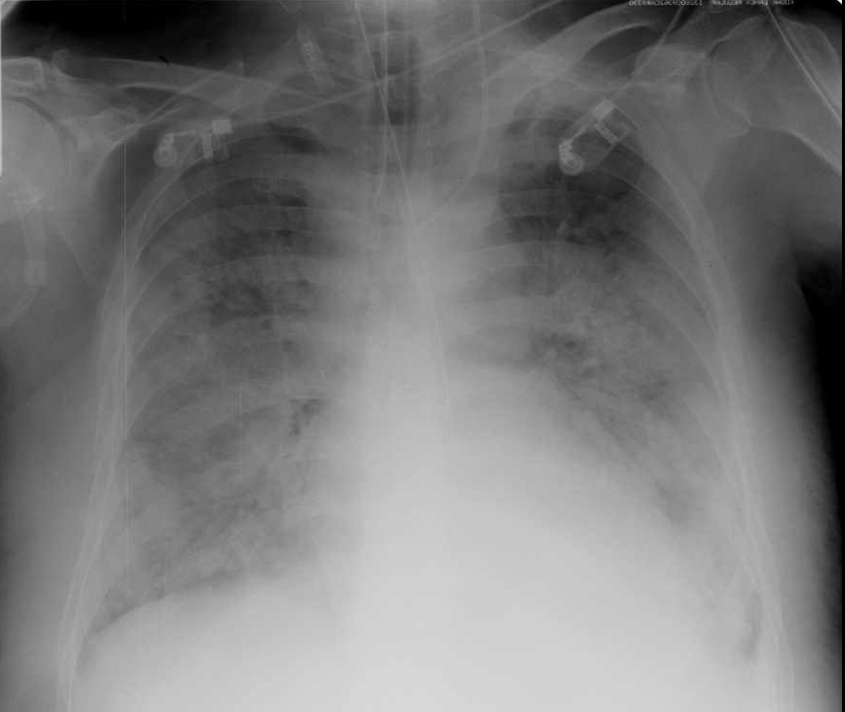

• ARDS: adult/ (acute) respiratory distress syndrome is a complication of the severely ill, usually ICU patients. It results in the severe loss of lung capacity. Diffuse alveolar injury leads to fluid leakage into the alveolar spaces that first appear as distinct alveolar consolidations. Later, they evolve to confluent patches of opacity (snow storm appearance).

14. Typical appearance of ARDS on chest X-ray: massive, bilateral consolidations with aerobronchograms.